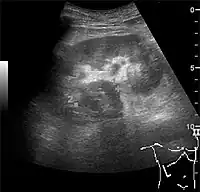

Figure 7. Advanced polycystic kidney disease with multiple cysts.[1]

Complex cysts can have membranes dividing the fluid-filled center with internal echoes, calcifications or irregular thickened walls. The complex cyst can be further evaluated with Doppler US, and for Bosniak classification and follow-up of complex cysts, either contrast-enhanced ultrasound (CEUS) or contrast CT is used (Figure 6). The Bosniak classification is divided into four groups going from I, corresponding to a simple cyst, to IV, corresponding to a cyst with solid parts and an 85–100% risk of malignancy.[1] In polycystic kidney disease, multiple cysts of varying size in close contact with each other are seen filling virtually the entire renal region. In advanced stages of this disease, the kidneys are enlarged with a lack of corticomedullary differentiation (Figure 7).[1]